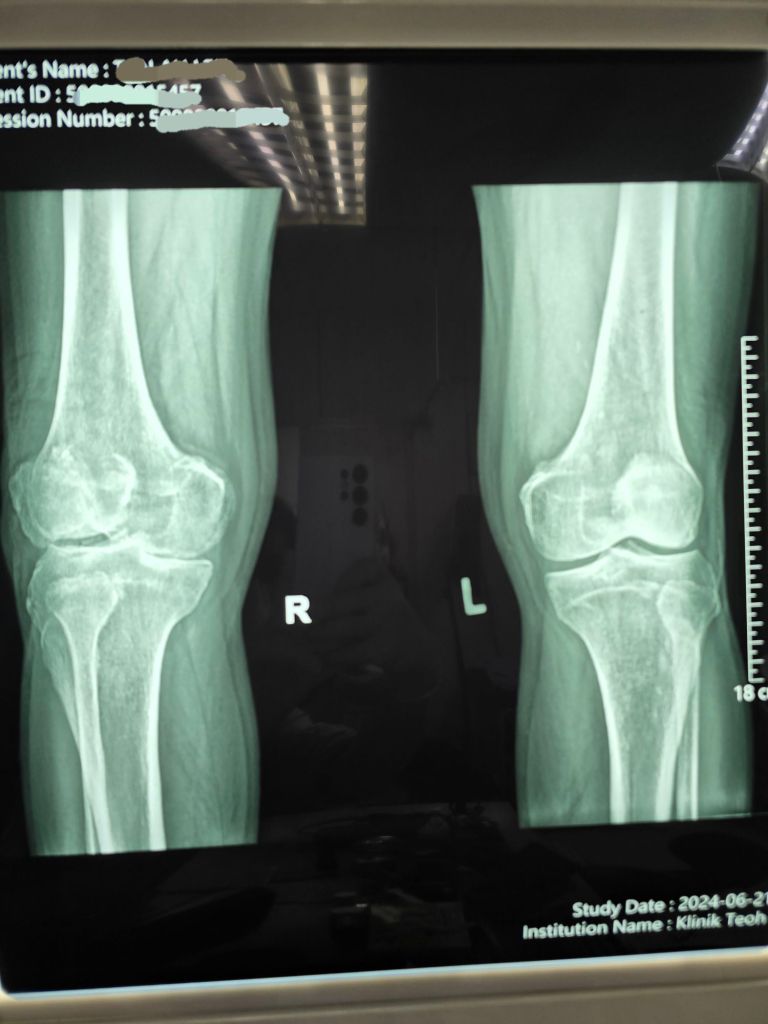

Diagnosis

Recent X-rays revealed advanced osteoarthritic changes in the right knee compared to the left, highlighting the severity of the degeneration.